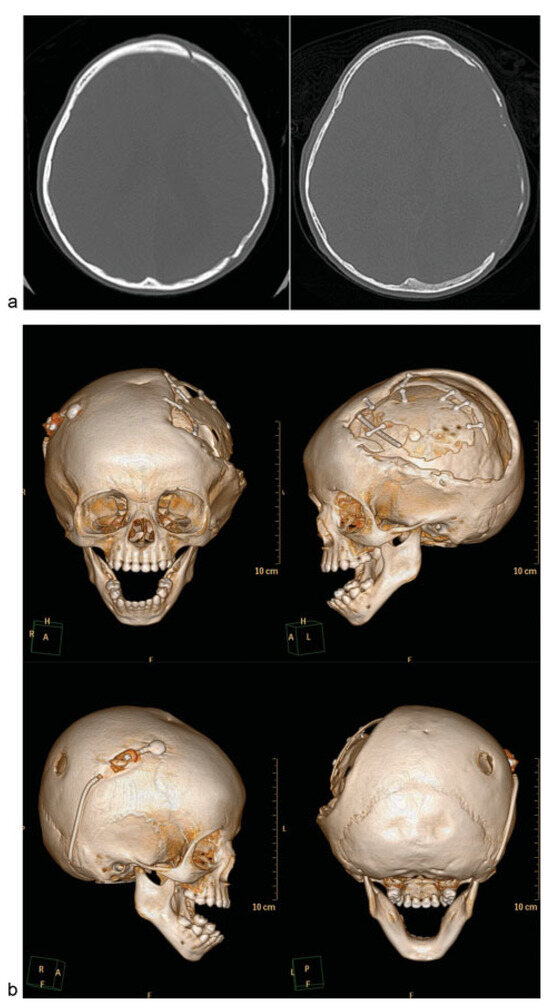

Autologous cranioplasty after decompressive craniectomy is considered the gold standard in pediatric care because of the ability of the bone graft to reincorporate into the skull (osseointegration), lower risk of material rejection, and ability to allow growth of the skull. There are several approaches to this form of reconstruction (Table 2). The three main ways to perform an autologous cranioplasty use bone stored in the body, cryopreserved bone, or bone flaps harvested from a donor site. With pediatric patients, additional considerations must account for the high incidence of bone resorption (Figure 1a–c), the immature osseous skeleton, and future growth.

Figure 1.

Case 1: An 18-month-old child with history of decompressive craniectomy for acute traumatic subdural hematoma, with at right frontal ventriculoperitoneal shunt in place for posttraumatic hydrocephalus. The autologous bone flap was retrieved from bone freezer storage and replaced 3 months after the initial trauma to repair the large left frontoparietotemporal skull defect. The autologous cranioplasty failed with bone flap resorption noted 6 weeks later, which was near complete by 4 months after autologous cranioplasty. An exchange cranioplasty was done, with re-siting of the ventriculoperitoneal shunt to the left occipital approach to avoid the bilateral cranioplasty areas. (a) Axial head computed tomographic (CT) scan immediately after autologous cranioplasty (left); axial CT scan of the same patient with bone flap resorption 4 months later (right). (b) Three-dimensional (3D) CT reconstructions showing bone flap resorption and right frontal ventriculoperitoneal shunt in place. (c) Axial CT scan (left) with corresponding intraoperative skull defect (right) at time of second reconstruction (exchange cranioplasty) after bone flap resorption. (d) Exchange cranioplasty. Measuring the donor site for the exchange and templating the cranial defect. (e) Exchange cranioplasty in process after placement of the freshly harvested contralateral bone graft. (f) Harvesting autologous particulates for bone grafting from the inner surface of a full-thickness calvarial flap. (g) Bilaminate mesh cranioplasty: inner layer of mesh in the right frontoparietotemporal calvarial defect, forming the epidural inner cortex. (h) Exchange cranioplasty completed with the recreated “diploic space” in between mesh layers filled autologous particulate bone mixed with demineralized bone matrix and autologous blood, then covered with the outer layer of mesh. (i) 3D CT scan 3 months after exchange cranioplasty showing partial consolidation of particulate graft on the left, incorporation of the full-thickness calvarial graft on the right with good skull contour. The shunt was re-sited to avoid the cranioplasty areas. (j) Axial CTscan 3 months after exchange cranioplasty.